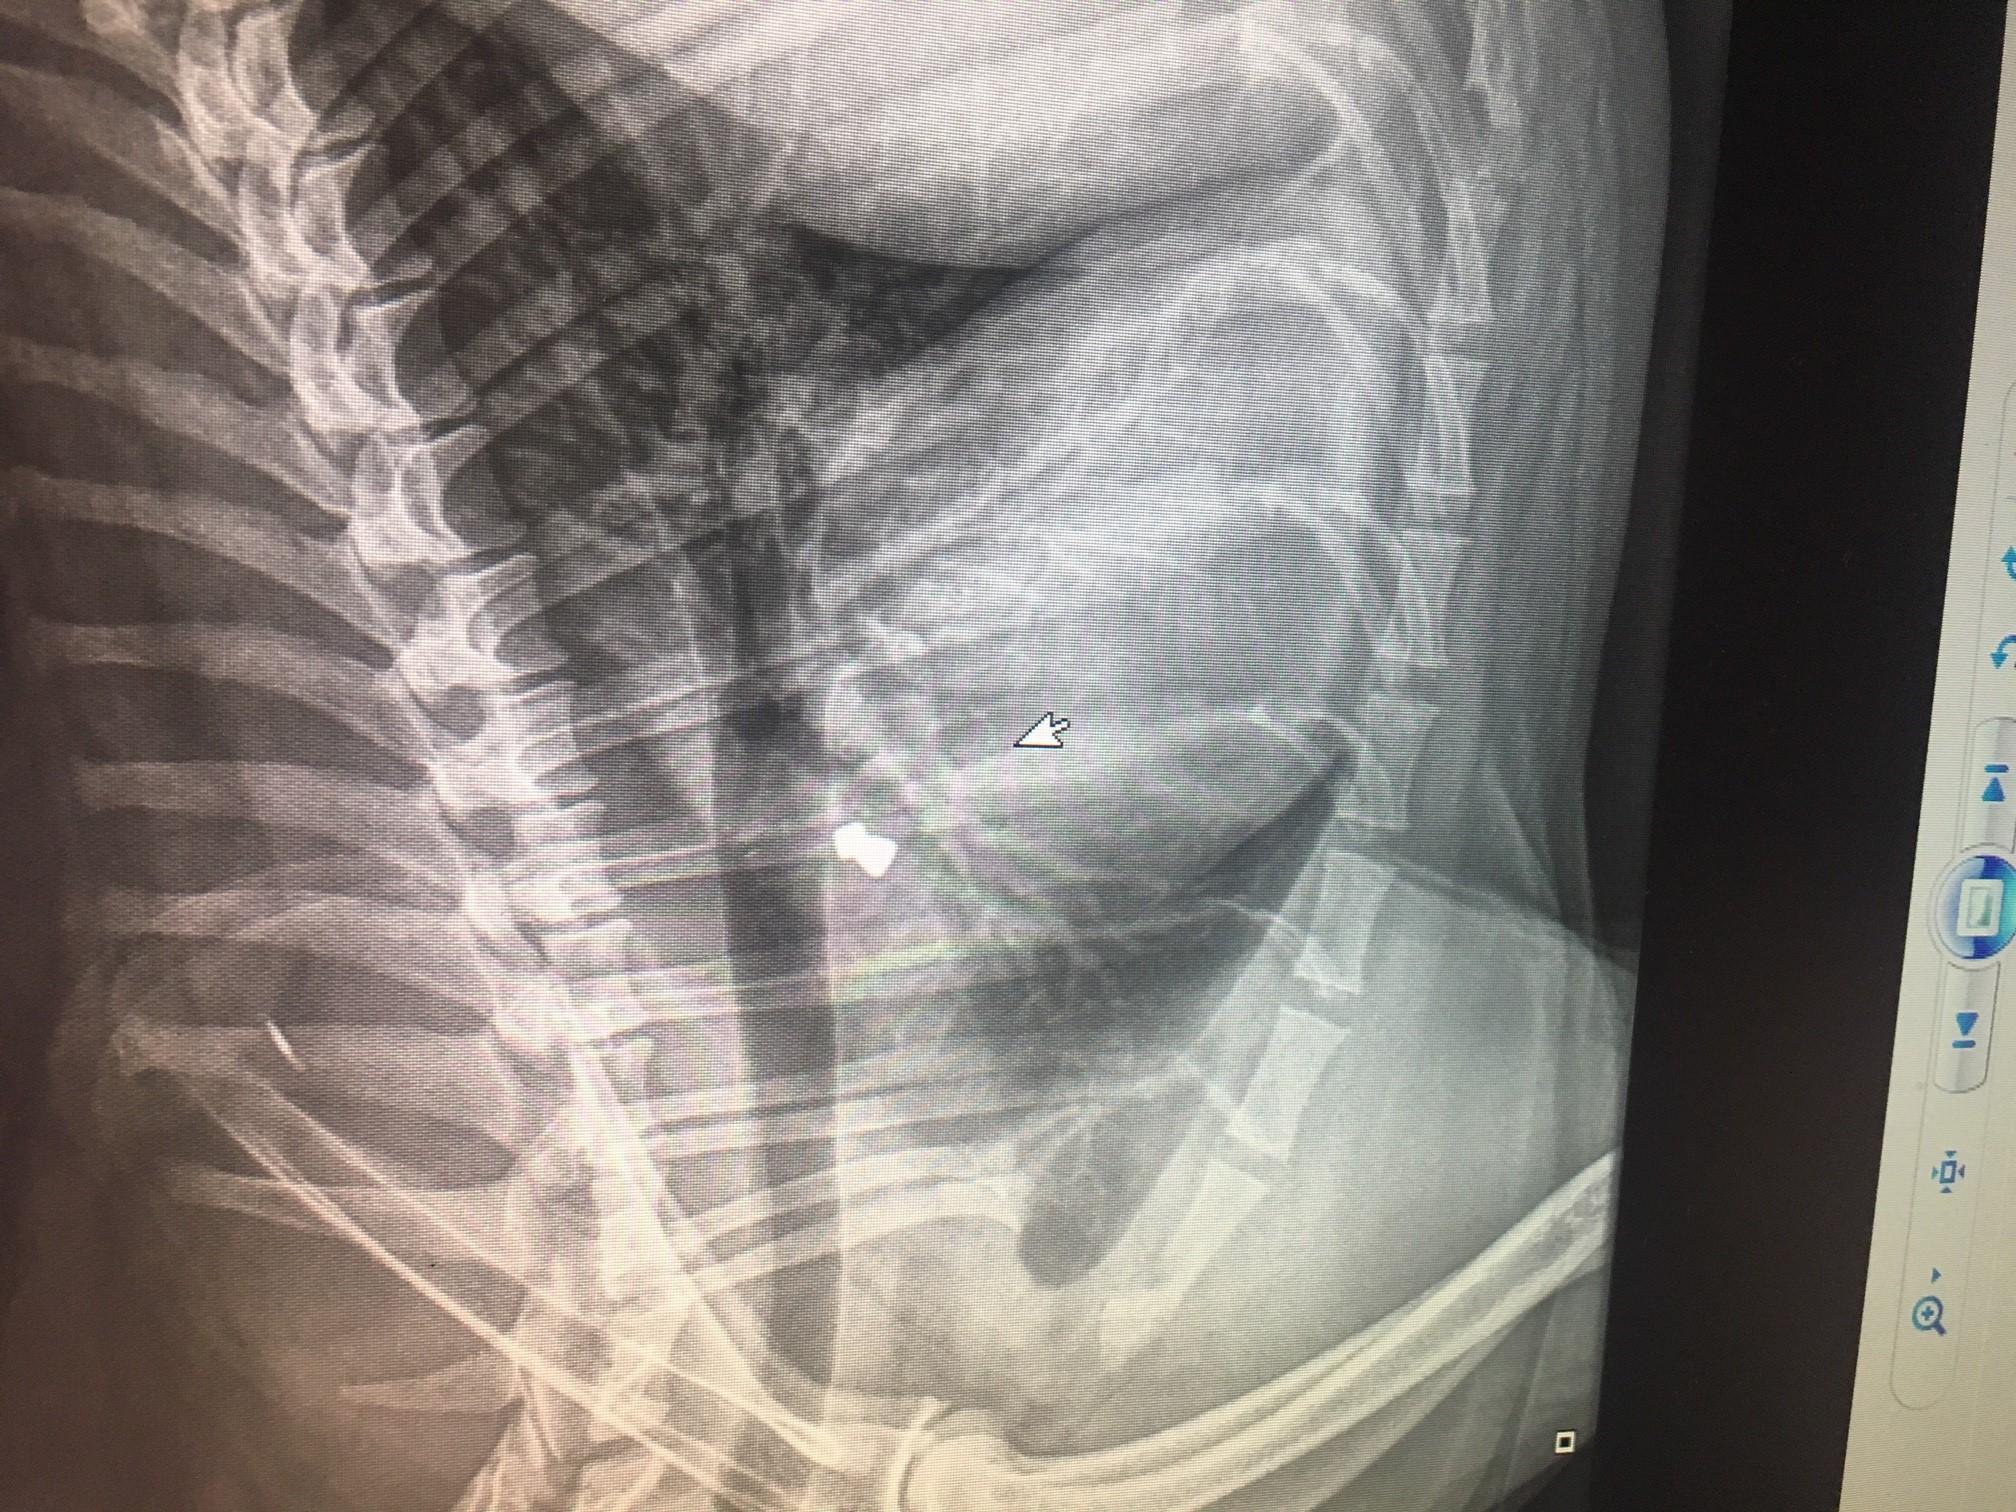

4. Cześć i czołem, Przesyłam najnowsze zdjęcie Pokrzywy. Zdjęcie dzisiejsze, ale pokazujące, co robiła Pokrzywa w poprzednim życiu ...neistety :( Na szczęście śrut niczemu nie przeszkadza, jest pod skórą i jest niegroźny. Tym niemniej...nadal nie mogę wyjść z szoku.